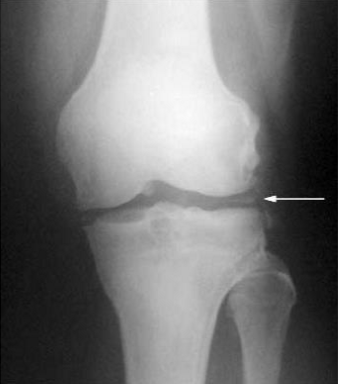

radiology - pyrophosphate arthropathy

occurs with the deposition of calcium pyrophosphate (crystals) [chondrocalcinosis]

can produce large & multiple subchondral cysts

narrowing of the patellofemoral joint space

metacarpal “hooks“

proximal migration of distal carpal row